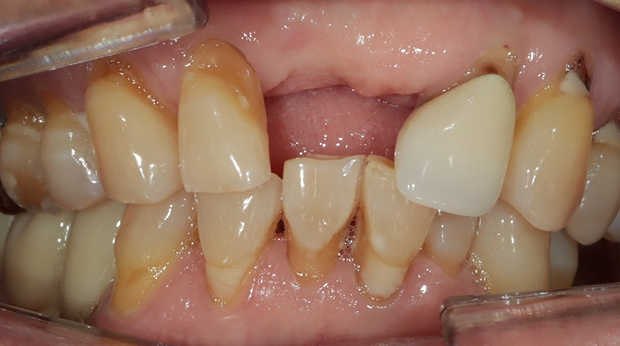

임플란트와 사랑니 발치는 외과적 시술로 잇몸을 절개하는 외과적 시술은

짧으면 짧을 수록 시술 후 붓기와 통증이 최소화됩니다.

치과의사 경력 14년차 구강외과 전문의가 빠르고 안전하게, 아프지 않게 수술해 드립니다.